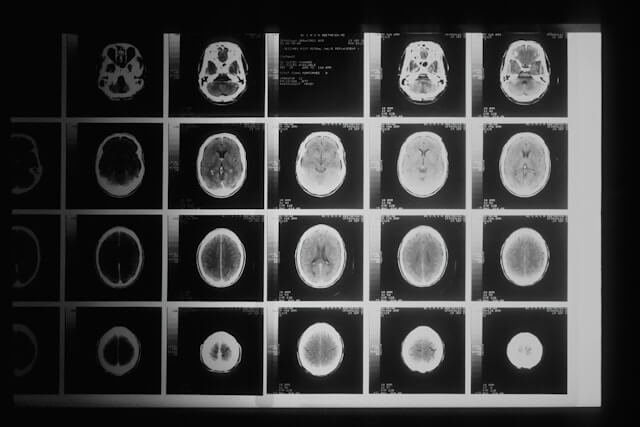

교모세포종은 뇌암 중에서 가장 흔한 형태 중 하나로, 뇌의 교질 조직에서 발생합니다. 이 암의 증상은 암의 위치, 크기, 그리고 성장 속도에 따라 다양할 수 있습니다. 공통적인 증상으로는 다음과 같은 증상이 있습니다. 첫 번째로 두통입니다. 두통은 특히 아침에 심하거나, 활동으로 인해 악화되는 경향이 있습니다. 두 번째는 구토 또는 메스꺼움입니다. 이러한 증상은 두통과 함께 나타날 수 있습니다. 세 번째는 시력 흐림, 이중 시력, 또는 시력 상실의 시력 문제가 발생할 수 있습니다. 네 번째는 말을 하기 어렵거나 이해하는 데 문제가 생기는 언어장애가 나타날 수 있습니다. 다섯 번째는 집중력 저하, 기억력 감소, 혼란 등의 인지 및 기억 장애가 나타날 수 있습니다. 여섯 번째는 근육 약화, 마비, 조정 장애 등으로 인한 운동 기능 장애가 발생할 수 있습니다. 일곱 번째는 기분 변화, 우울증, 불안 등의 성격 변화 또는 정서적 변화가 나타날 수 있습니다. 마지막으로 갑작스러운 의식 상실, 경련, 또는 감각 이상과 같은 간질성 발작을 경험할 수 있습니다. 이러한 공통적인 증상이외에 교모세포종이 발병한 뇌의 위치에 따라서 다른 증상이 나타나기도 합니다. 먼저 전두엽의 경우 성격 변화, 운동 기능 장애, 계획 및 판단 능력 저하 등이 나타날 수 있습니다. 측두엽은 기억 장애, 시청각 장애, 언어 이해 또는 말하기 문제 등이 발생할 수 있습니다. 후두엽의 경우 시각 장애가 주요 증상입니다. 마지막으로 두정엽의 경우 감각 장애, 공간 감각 상실, 운동 조정 문제 등이 나타날 수 있습니다.

교모세포종의 치료방법은 크게 6가지로 분류됩니다. 첫 번째는 수술적 치료입니다. 수술이 가능한 경우, 교모세포종을 제거하기 위한 첫 번째 치료 방법입니다. 완전히 제거가 어려운 경우에도, 가능한 많이 암 조직을 제거하여 증상을 완화시키고, 다른 치료 방법의 효과를 높일 수 있습니다. 두 번째는 방사선 치료입니다. 수술 후 남은 암 세포를 파괴하거나, 수술이 불가능한 경우 암의 성장을 억제하는 방법입니다. 외부 방사선 치료(EBRT)와 같은 전통적인 방사선 치료뿐만 아니라, 정밀한 방사선을 이용하는 입체 조형 방사선 치료(SRT), 감마나이프 치료와 같은 고정밀 방사선 치료 방법도 있습니다. 세 번째는 화학 요법입니다. 암 세포의 성장을 억제하기 위해 특정 약물을 사용합니다. 테모졸로마이드(Temozolomide)와 같은 약물이 주로 사용되며, 이는 수술 후 및/또는 방사선 치료와 병행하여 사용됩니다. 네 번째는 표적 치료입니다. 암세포의 특정 유전자나 단백질, 그리고 암세포 성장에 필수적인 조직 환경을 대상으로 하는 치료 방법입니다. 이는 정상 세포에는 적은 영향을 주면서 암세포만을 표적으로 합니다. 다섯 번째는 면역 치료입니다. 최근에는 환자의 면역 체계를 활용하여 암 세포를 공격하도록 하는 치료 방법이 연구되고 있습니다. 이러한 치료는 아직 초기 단계이지만, 일부 환자에게 효과적일 수 있습니다. 마지막으로 임상 시험입니다. 기존의 치료 방법 외에도, 새로운 치료법을 시험하는 임상 시험에 참여하는 것도 한 방법입니다. 새로운 약물, 치료 조합, 또는 접근 방식을 탐색할 수 있습니다. 교모세포종은 가장 공격적인 형태의 뇌암 중 하나로, 세계보건기구(WHO)에서 등급 IV로 분류된 고위험군 암입니다. 이러한 고위험군 뇌암은 치료를 진행하여도 빠르게 진행되며, 생존율이 매우 낮습니다. 교모세포종의 5년 생존율은 대략 5%에서 10% 사이입니다. 다른 암에 비하여 매우 낮은 생존율로서, 이 수치는 교모세포종의 공격적인 성격과 치료에 대한 난이도를 보여줍니다. 낮은 생존율이지만 환자의 나이, 건강 상태, 암의 정확한 위치와 크기, 치료를 얼마나 빨리 진행했는지에 따라서 생존율이 달라질 수 있습니다.